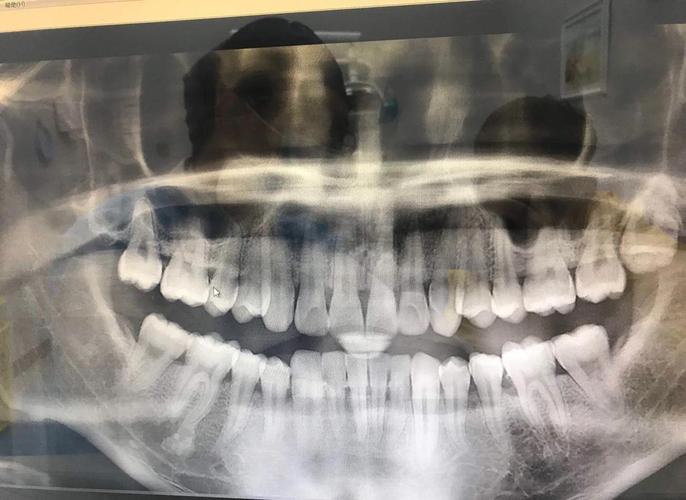

矫正期间发现长智齿,该如何科学处理呢?核心原则是“定期检查,动态评估,个体化处理”,正畸患者需每3-6个月进行一次口腔检查,拍摄全景片(曲面断层片),观察智齿的萌出状态、位置以及与邻牙、矫正牙的关系,医生会根据智齿的类型(如垂直阻生、水平阻生、近中阻生等)、萌出方向、是否有临床症状以及对矫正进程的潜在影响,制定处理方案。